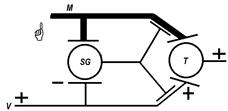

С тех же позиций можно объяснить фантомные боли при ампутации конечностей (рис.): желатинозная субстанция не имея не имея влияний со стороны неноцицептивных афферентов удаленной конечности не тормозит ноцицептивные афференты других областей тела и нейрон Т пропускает ноцицептивные импульсы к высшим отделам, которые воспринимаются как импульсы с удаленных конечностей (как отраженные боли, отраженные сознанием на удаленную конечность[Б18]).

Рис.. Объяснение фантомной боли по теории воротного контроля.